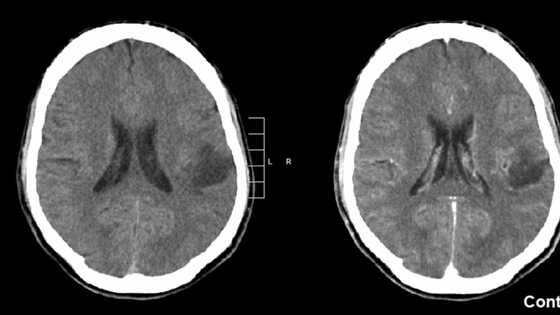

Издание Frontiers in Psychiatry рассказало о весьма необычном случае, который произошел с 48-летней женщиной, поступившей в одну из швейцарских больниц. У нее нашли многочисленные раны груди, глубина которых достигала 7 см. Женщина заявила, что нанесла ранения себе сама, поскольку ей приказали так сделать «божественные голоса». Причем речь, по ее словам, шла о «религиозном самопожертвовании». После этого сотрудники больницы пригласили психиатров, однако проблема, как оказалась, крылась не столько в сфере их компетенции, сколько в сфере компетенции онкологов. Пациентка заявила, что на протяжении трех последних лет ощущала себя «благословенной» и общалась с голосами, возникавшими у нее в голове. Сама она полагала, что они «исходят с небес». По словам женщины, было два голоса, с которыми она могла общаться долгие часы и которые разговаривали с ней на самые разные темы. В зависимости от направления общения она чувствовала себя испуганной или же, наоборот, ощущала защиту и благословение. Как выяснили медики потом, на протяжении всей жизни пациентка несколько раз переживала всплески религиозности, которые потом шли на убыль. Причем впервые она столкнулась с чем-то подобным еще в 13 лет. Получив общую картину, психиатры пришли к заключению, что женщина страдает от психоза. Было решено провести МРТ. Именно оно показало наличие опухоли мозга — злокачественной глиомы. По словам одного из авторов исследования Себастьяна Вальтера (Sebastian Walther), опухоль, вероятно, возникла еще в раннем возрасте и росла на протяжении всей жизни чрезвычайно медленными темпами, периодически влияя на поведение пациентки. Медики не могут полностью определить механизмы воздействия опухоли на взгляды и переживания больной. Специалисты полагают, что при разрастании глиома начала оказывать давление на прилежащие области мозга, ответственные за обработку звука и влияющие на формирование эмоций. В конечном итоге это вызвало религиозный подъем и слуховые галлюцинации. Расположение опухоли не позволяет провести операцию по ее удалению. Поэтому медики сделали все, что могли в данной ситуации, а именно выписали больной антипсихотические препараты. Они на некоторое время затормозили развитие галлюцинаций. Однако последние появились вновь после снижения доз.